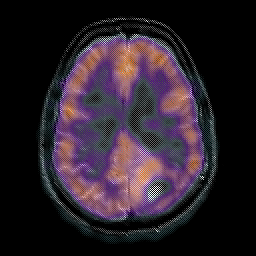

Glioma overlay -- Slice #19

[Home][Help][Clinical] Slice 19